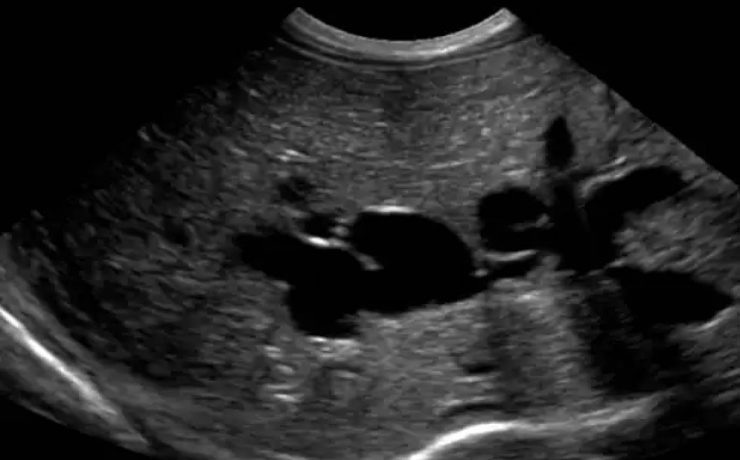

BAZO ACCESORIO SIMULANDO TUMOR SUPRARRENAL

El diagnóstico de los así llamados “incidentalomas” suprarrenales, cada vez más frecuente en la práctica clínica, plantea un diagnóstico diferencial importante. Caso clínico: Se presenta el caso clínico de una paciente de 69 años, hipertensa, con el hallazgo de una masa suprarrenal izquierda aparentemente funcionante, operada por vía laparoscópica y